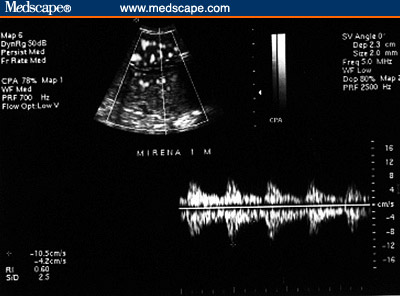

Figure 5. LNG-IUS. Subendometrial flow. (5A, 1 month

post-insertion [Note the rich flow]; 5B, 5 months post-insertion

[Note the lack of subendometrial flow]).

defined as the control group). There was no significant difference between the

2 groups with regard to Doppler flow in the cervical branch of the uterine

artery (resistance index (RI) = 0.6 ± 0.01 in both groups, P = .9)

[see footnote†]. Endometrial width was